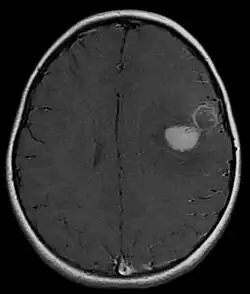

Supratentorial central PNET in a 5-year-old patient

PNET of the CNS generally refer to supratentorial PNETs.

The approach to management of a CNS PNET is first to obtain detailed imaging through MRI, as well as additional scans of the patient's body (X-ray, CT, PET, even bone marrow biopsies) to look for metastasis or other associated malignancies. The tumor will then need to be biopsied to confirm the diagnosis. After the diagnosis of a CNS PNET is confirmed, management includes neoadjuvant chemotherapy and radiation (to reduce tumor size burden), complete surgical resection with confirmed negative margins, and/or additional adjuvant post-surgical chemotherapy. CNS PNET is aggressive and must be managed as so. Palliative care services should also become involved in the patient's care team when the diagnosis is made. [6]